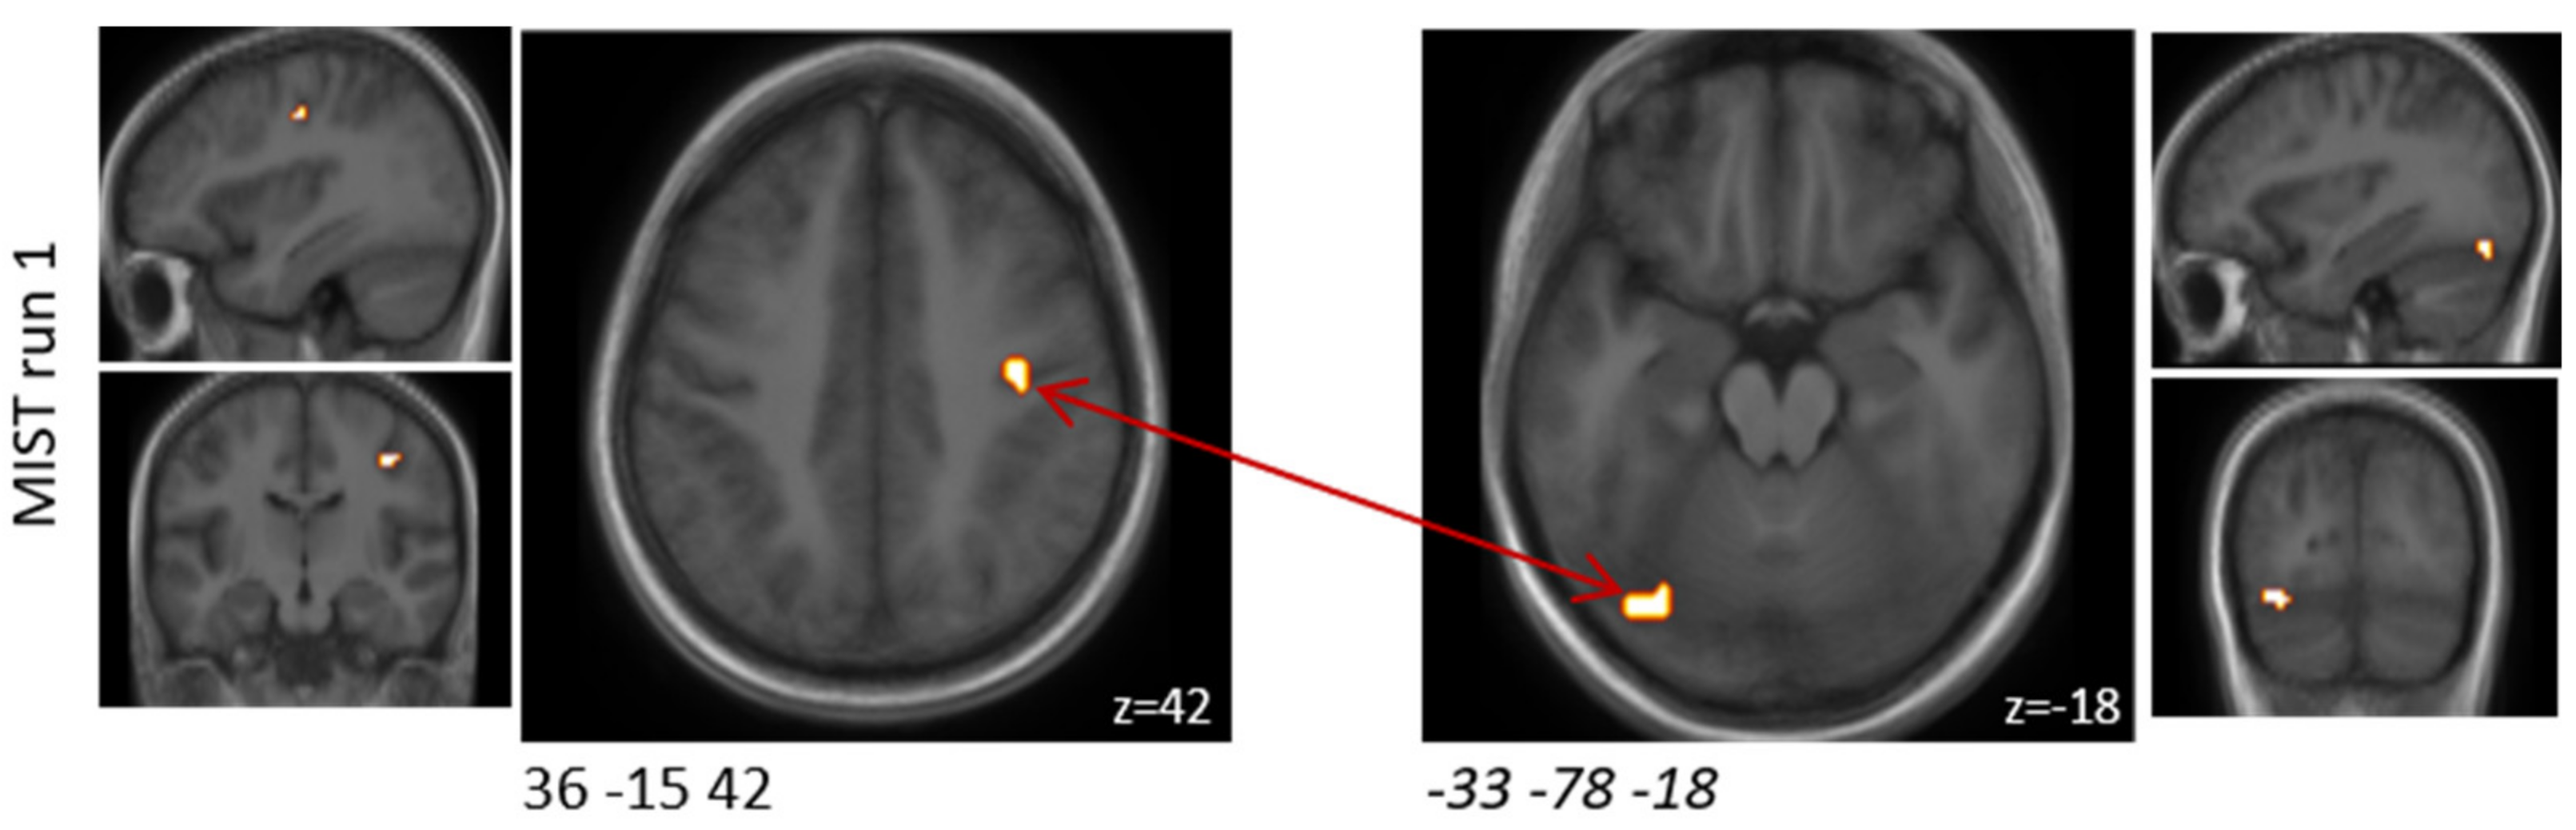

3.5. Probiotics Significantly Affected Functional Brain Connectivity during MIST

In order to understand how the probiotic intervention altered task-related functional connectivity, a connectivity analysis was performed between all clusters that were found to be differentially activated when comparing the experimental and the control condition after the placebo intervention.

In MIST run one, functional connectivity between two of these clusters was found to be significantly (FDR-corrected p = 0.02) increased by the probiotic intervention (Table 3 and Figure 3). These two clusters were located in the upper limbic and medioventral regions; the latter was among the predefined ROIs. During the MIST runs two and three, no alterations in functional connectivity were observed.

Clusters that were found to be associated with significant functional connectivity changes between both interventions during the MIST paradigm. One of these clusters covered a predefined ROI (italic).

Figure 3.

Schematic visualisation of clusters that were found to be associated with significant (FDR-corrected p < 0.05) functional connectivity changes when comparing the probiotic and the placebo interventions (probiotic > placebo) during the MIST paradigm. One of these clusters covered a predefined ROI (italic). Clusters are superimposed on average anatomical scans. Clusters can be identified by the coordinates of their peak (x y z).